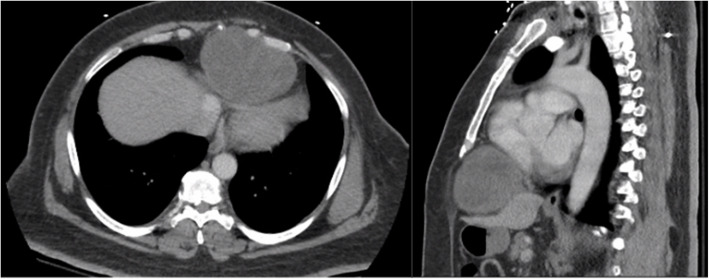

神经鞘瘤是后纵隔最常见的神经源性肿瘤,但在前纵隔很少发现(mediastinum 4,2020;中华放射医学杂志13(4):175-7。我们报告一个大的前纵隔神经鞘瘤引起心脏压迫,同时颈椎病变引起右侧无力。目前文献中只有少数病例报告描述了这种肿瘤的前位,更罕见的是同时有症状性宫颈病变。我们提出这个病例是为了强调这种罕见的发现,并提高对这种潜在诊断的认识。

Schwannoma is the most common neurogenic tumor in the posterior mediastinum, however it is rarely found in the anterior mediastinum (Mediastinum 4, 2020; Radiat Med 13(4):175-7). We report a large anterior mediastinal schwannoma causing cardiac compression along with a concurrent cervical spine lesion causing right-sided weakness. Current literature having only a few case reports describing an anterior location for this neoplasm and even rarer to have a concurrent symptomatic cervical lesion. We present this case to highlight this rare finding and increase awareness of this potential diagnosis.